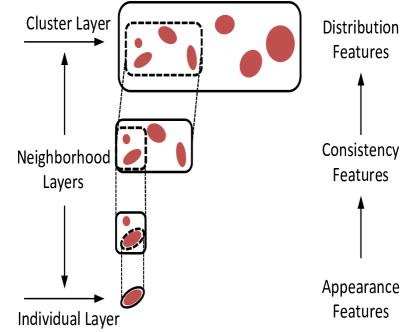

The proposed hierarchical model is shown in Figure 2. The model is composed of multiple connected layers. Each layer represents areas of interest associated with the target objects. The area of interest is the “scope” of the object.

The bottom layer is called “individual layer”, which focuses on individual objects (or parts of objects). The scope of this layer is closely around the individual object, and the objects are treated independently from each other.

The topmost layer is called “cluster layer”, which represents the entire group of objects. The scope of this layer includes all the objects in the group.

The layers between individual layer and cluster layer are called “neighborhood layers” that handle the relationship among objects. The scopes of these layers depend on the number of objects to compare. Multiple neighborhood layers can be created with different scopes.

The model also guides feature extraction at each layer. Close to the individual layer, appearance features for individual object should be extracted. Then consistency measurements should be added to the feature set when system processing the neighborhood layers. Close to the cluster layer, the feature set expands to include distribution measurement of objects within groups. Please note that the model only provides a guidance and there is no clear boundary of where each type of features has to be computed.

Furthermore, the concept of “scope” plays an important role to extract robust features within each layer. One possible usage is to use normalization within each of the local scopes as stated below.

With scope-based normalization, local contrast of the individual objects is enhanced in the lower level of the layers, and the consistency among neighboring objects can be uniformly evaluated in the neighborhood layers.